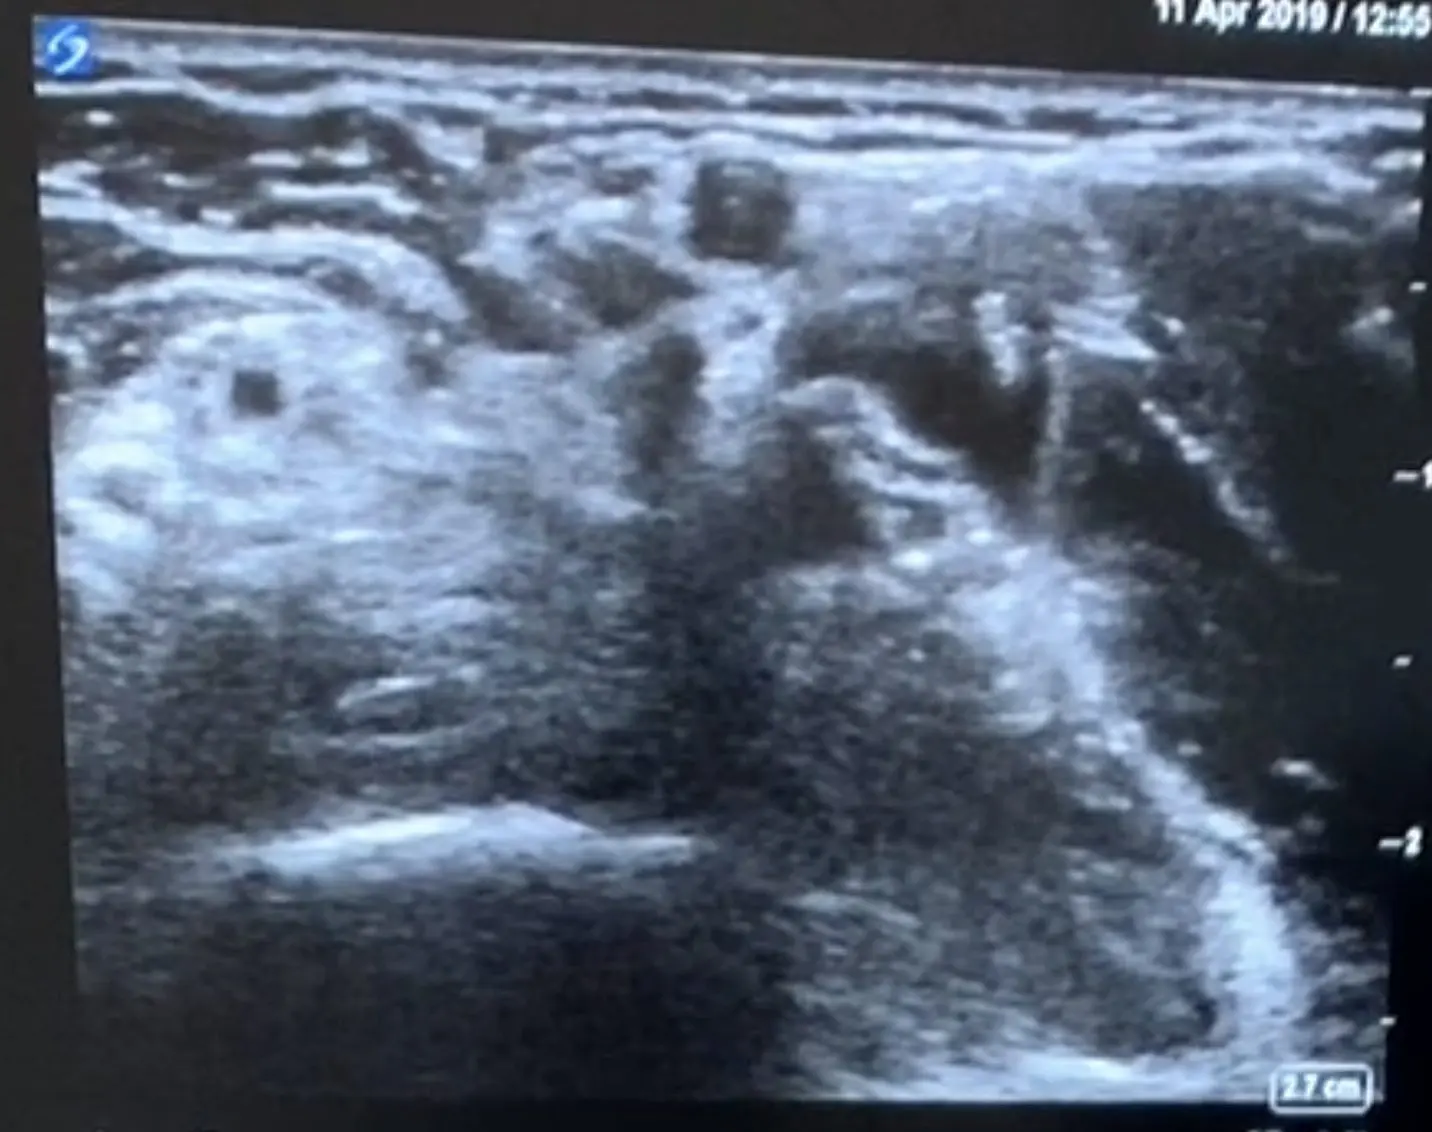

下記は40代女性右手を酷使する仕事で右手の前腕の痺れと痛みで来院、他院では頸椎症性神経根症として牽引などの治療されていましたが、身体所見からそちらは一度除外し前腕にエコーを当てたところ下記の所見がありました。

エコーでは両方の神経の周りがもやもや白くなっているのがわかりますよね

病名は円回内筋症候群 絞扼疾患の一つです

剥離後

正中神経を剥離しました。剥離前は周り全体が白かったですが、剥離後は神経が明確に描出されていることがわかります。